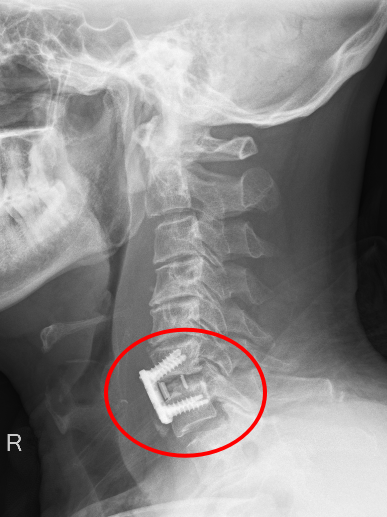

患者朱先生因意外從高處墜落,頸部劇痛、四肢麻木無(wú)力,急診入院后經(jīng)CT及MRI檢查確診為第6頸椎骨折脫位伴脊髓損,隨時(shí)可能引發(fā)呼吸衰竭或永久性癱瘓。傳統(tǒng)保守治療風(fēng)險(xiǎn)極高,骨科主任彭李華主任醫(yī)師及脊柱專(zhuān)業(yè)組長(zhǎng)張利強(qiáng),迅速組織多學(xué)科會(huì)診,結(jié)合國(guó)際最新指南與患者個(gè)體情況,果斷制定“前路頸椎間盤(pán)切除+植骨融合內(nèi)固定術(shù)”方案,以微創(chuàng)技術(shù)最大限度減少神經(jīng)損傷,脊髓受壓明顯減輕,重建頸椎穩(wěn)定性。

術(shù)后影像顯示,頸椎序列完美復(fù)位,內(nèi)固定位置精準(zhǔn),患者次日即感雙上肢麻木緩解,肌力較術(shù)前明顯改善,術(shù)后第二天,患者頸部及雙上肢疼痛癥狀消失,在頸托保護(hù)能自主下床行走,術(shù)后一周痊愈出院。